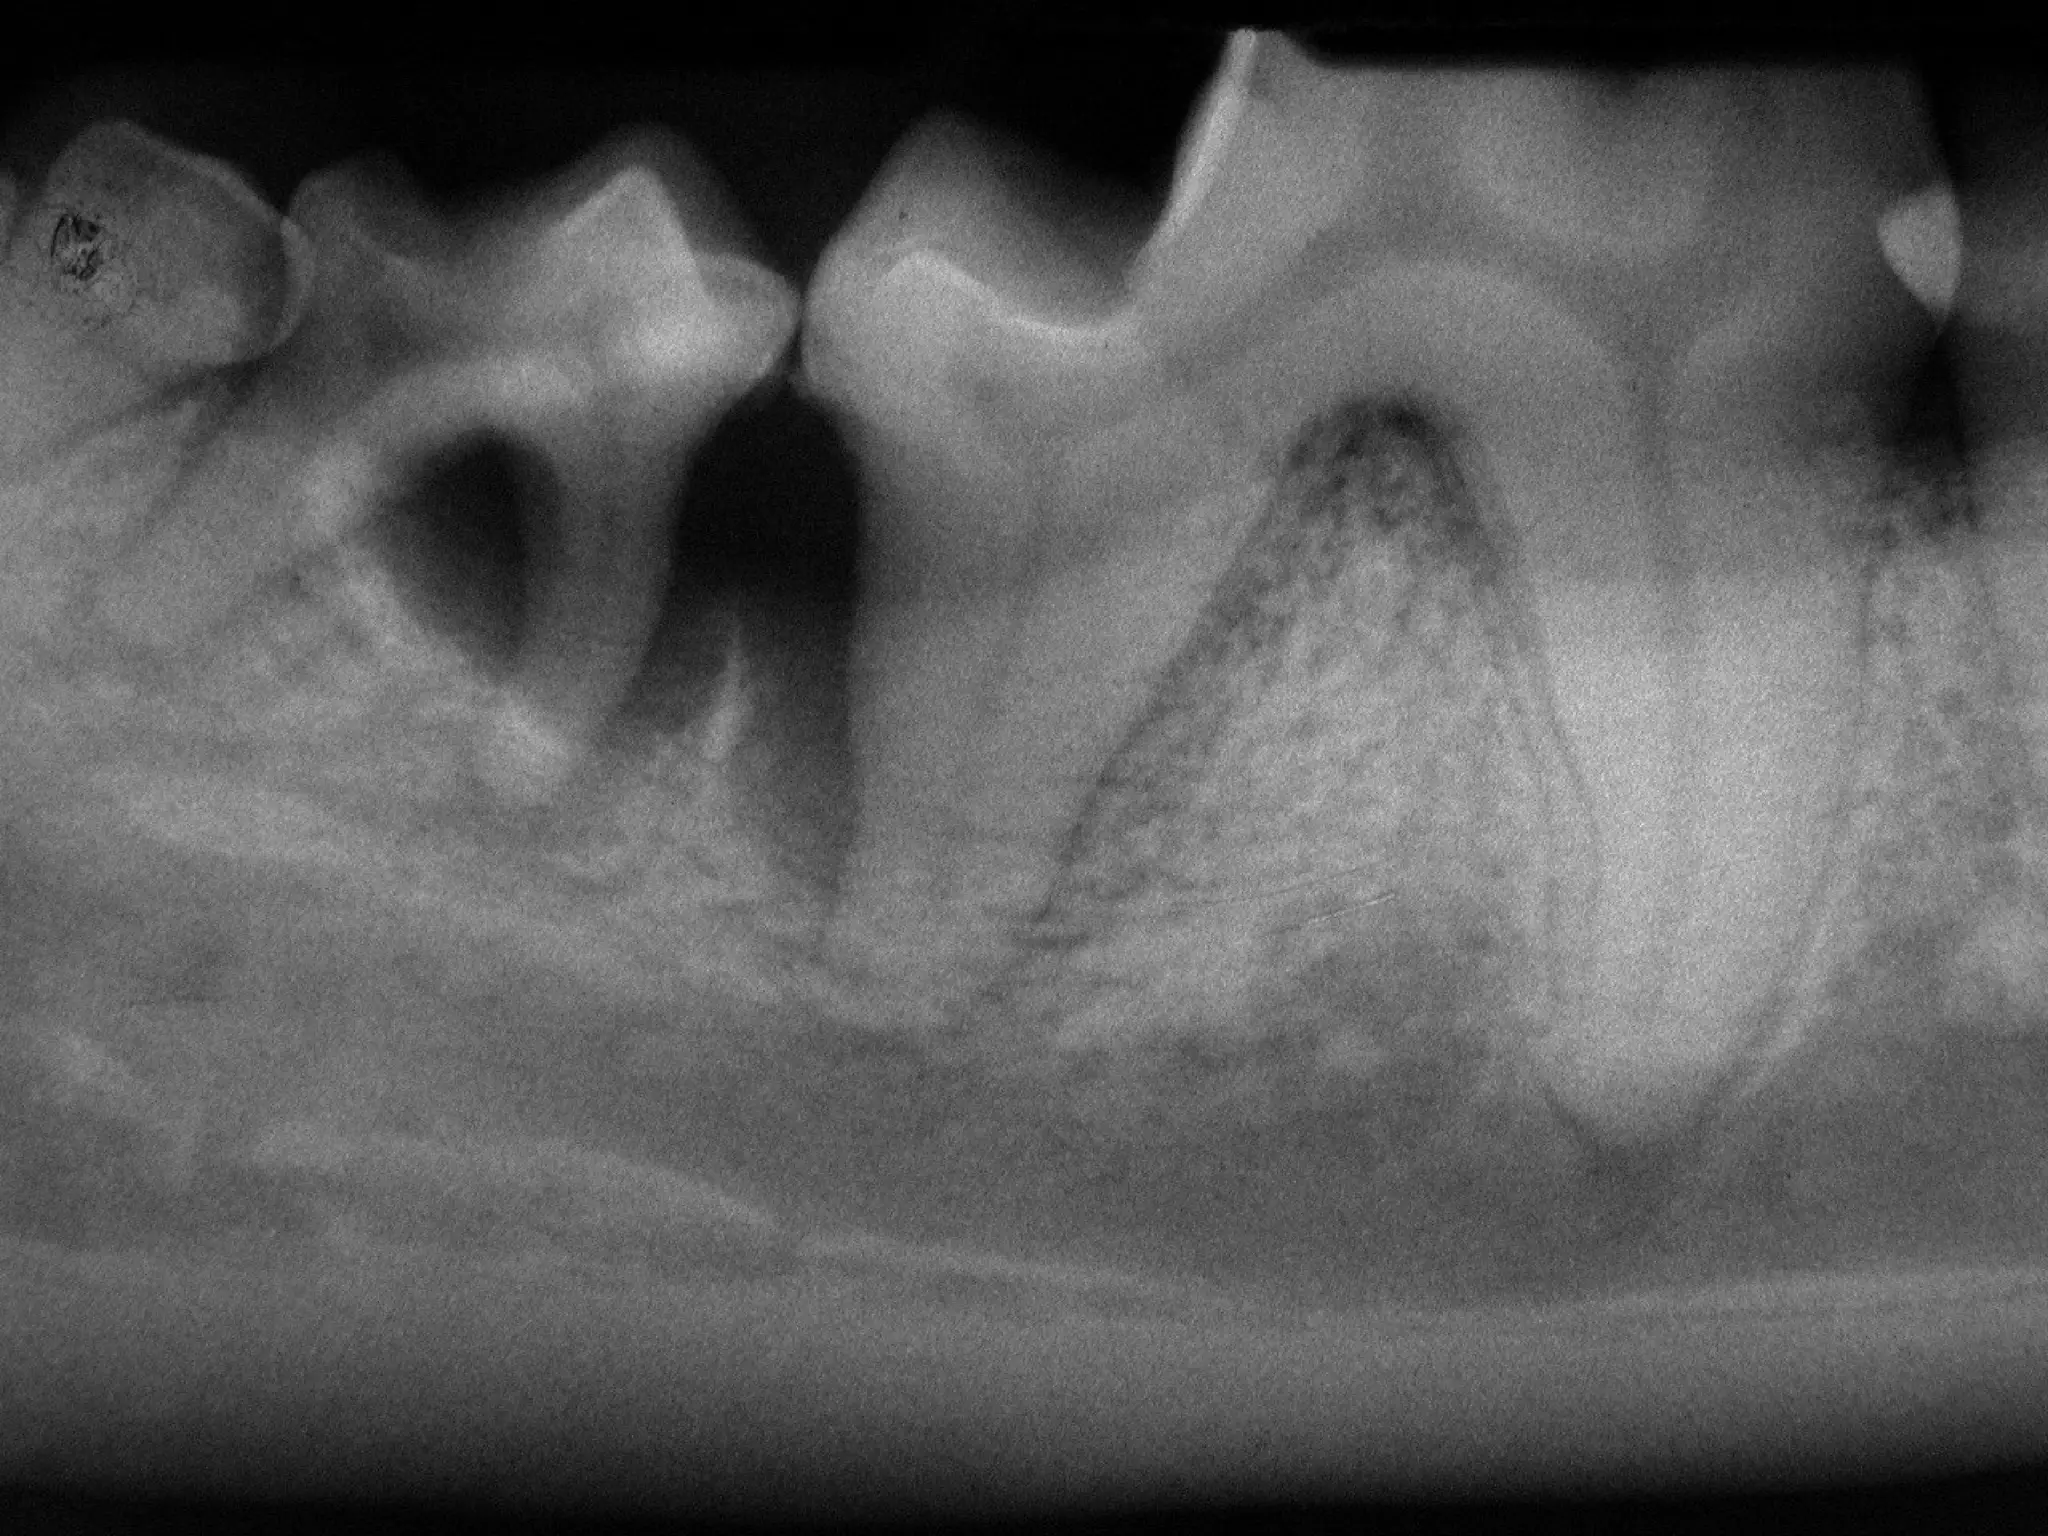

What disease is affecting the area

surrounding these teeth?

Is this the patient’s right or left

mandible?

What disease isaffecting the area surrounding these teeth? Is this the patient’s right or left mandible? 2